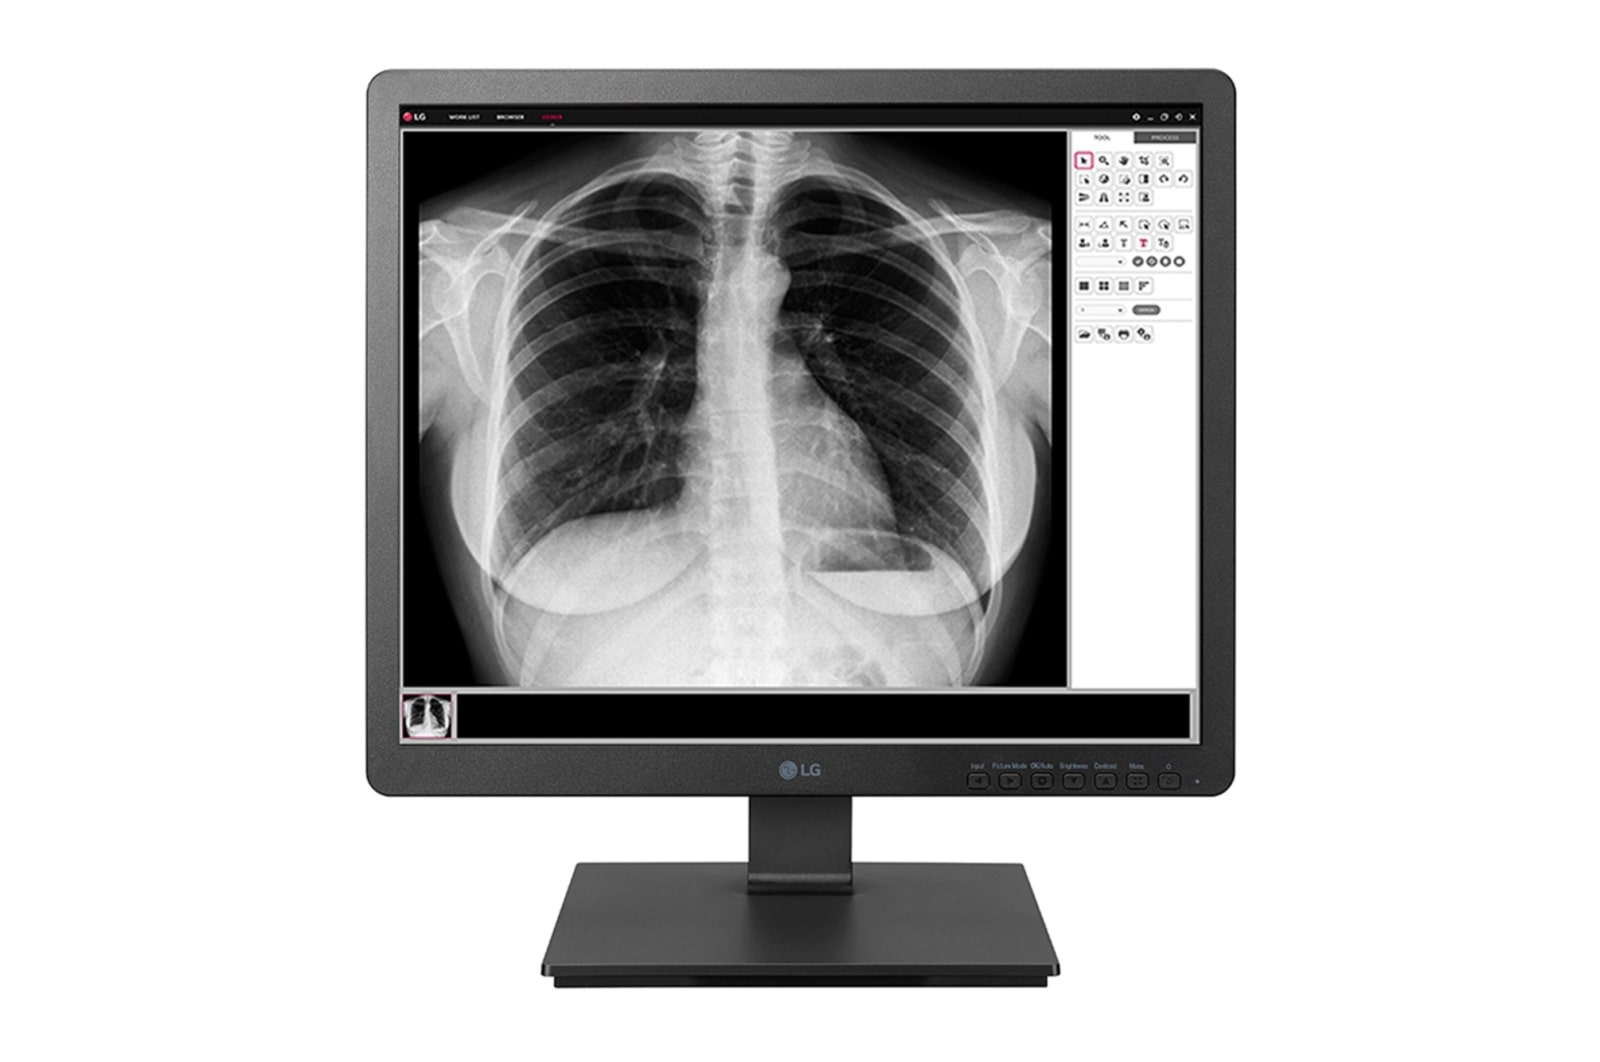

19" medical monitor